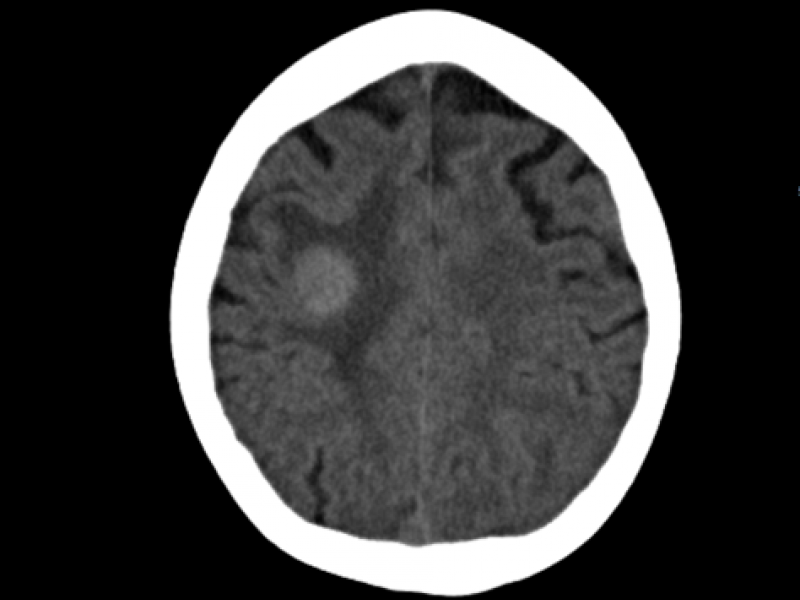

A 42 yo male presents to the ED after he was assaulted. He